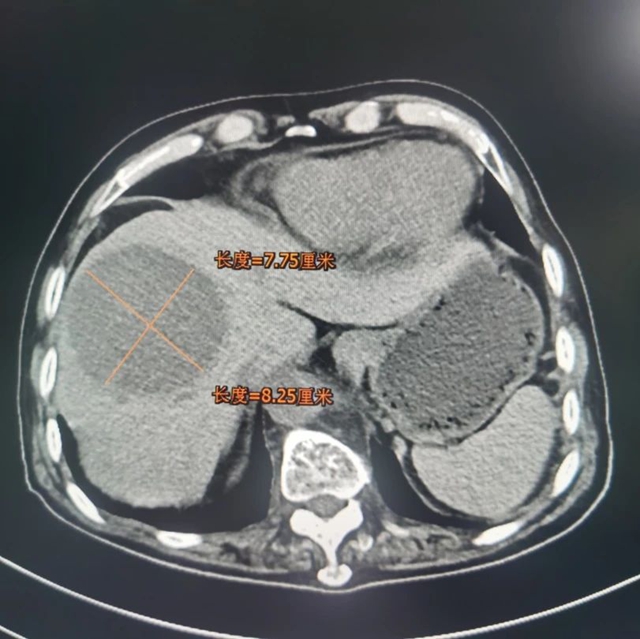

70多岁的喻大爷体检时发现肝脏占位性病变,刚开始并没有在意,谁知没过多久大爷开始出现肝区(右季肋部)疼痛,熬了几天实在受不了,喻大爷赶紧来到西南医科大学附属中医医院肝胆病科就诊。完善相关检查后,发现肿瘤达11.07cm*12.25cm,肿瘤指标略偏高,进一步经肝穿刺病检,最终确诊为原发性肝癌。

考虑到大爷肿瘤较大,且年龄较大,整体身体状态较差,肝胆病科团队为其实施了“肝动脉造影+灌注化疗栓塞术”,术后在西医治疗基础上口服中药制剂和枢消积丸,随后加入科室四川省科技厅重大专项研究中进行规范随访。4个月复查,喻大爷肿瘤已明显缩小至7.75cm*8.24cm。

术前

术后

对比肿瘤明显缩小